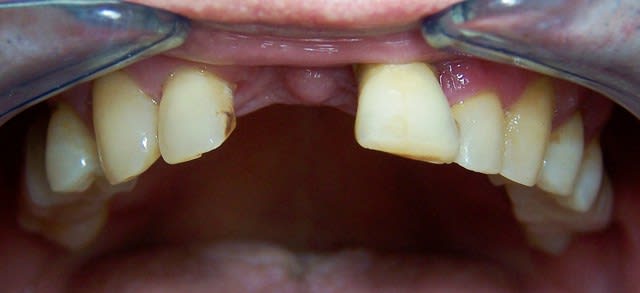

Au stade de la pano 1 peut-on sauver les dents ?

Le patient a eu un traitement paro suivi d’une contention ortho. Une option était exo 11 21 25 et bridge 15 à 25, mais 13 14 15 étaient latéro déviées cela se devine sur la photo que Noah a reprise.

planif cas 1